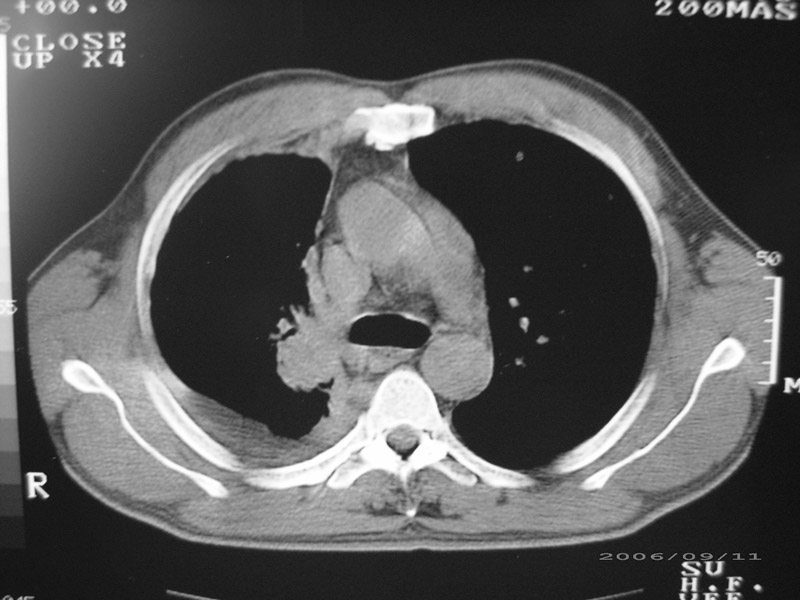

以下是引用守望可可西里在2006-9-11 15:29:00的发言:[br][br] ct平扫表现:右侧胸膜腔缩小,积液,胸膜增厚且不均匀、不规则,以纵隔胸膜增厚为主,边缘呈锯齿状,并见附壁内突之结节状肿块影。右肺含气量减少,纹理聚集,右肺门中下部见数个肿大的淋巴结。纵隔无移位,内未见明显肿大淋巴结,双侧主支气管以及各叶、段支气管比较通畅。。[br] 考虑:右侧胸膜恶性间皮瘤,伴肺门淋巴结转移。